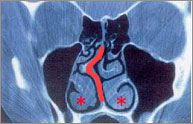

これを鼻中隔矯正術といいます。下の患者さんは、右に凸の鼻中隔彎曲症です(オレンジ太線)。また、特に左側に肥厚性鼻炎を認めます。

鼻 腔の側壁から出ているヒダのようなものを下鼻甲介(上記写真の「*」部分)といいます。粘膜が厚かったり、骨がとび出ていたりすると肥厚性鼻炎になりま す。症状は、とにかく鼻が一日中詰まりっぱなしで、点鼻薬(血管収縮剤)もだんだんと効果がなくなってきます。これを直すのが、粘膜下下甲介骨切除術(と びでている骨を削る)、下鼻甲介粘膜切除術(厚くなった粘膜を削る)です。